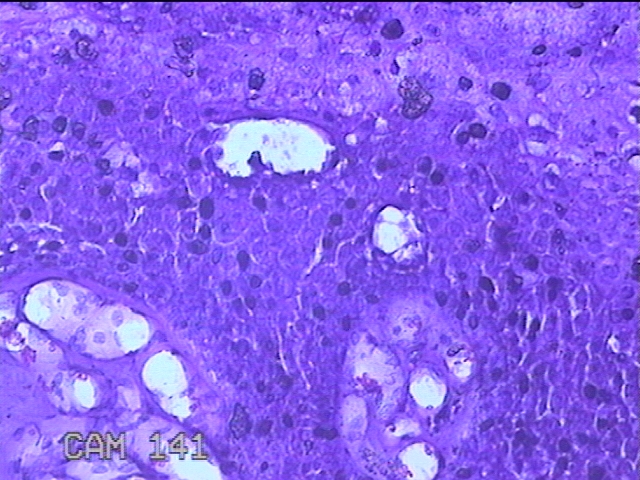

尿道口肿物

性别

男

年龄

46岁

临床诊断

尿道肿物

一般病史

发现尿道口肿物10余天。

标本名称

大体所见

灰白粉红色不规则肿物0.8x0.5x0.2一堆。

似有挖空细胞,有可能要考虑湿疣,片子这个效果,真是不敢猜。